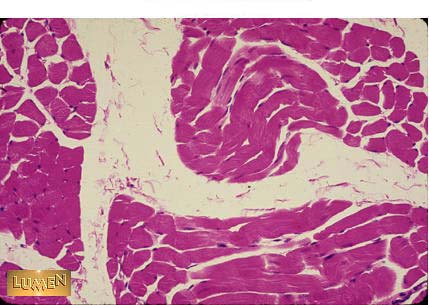

Identify the tissue?

Answer

Skeletal Muscle